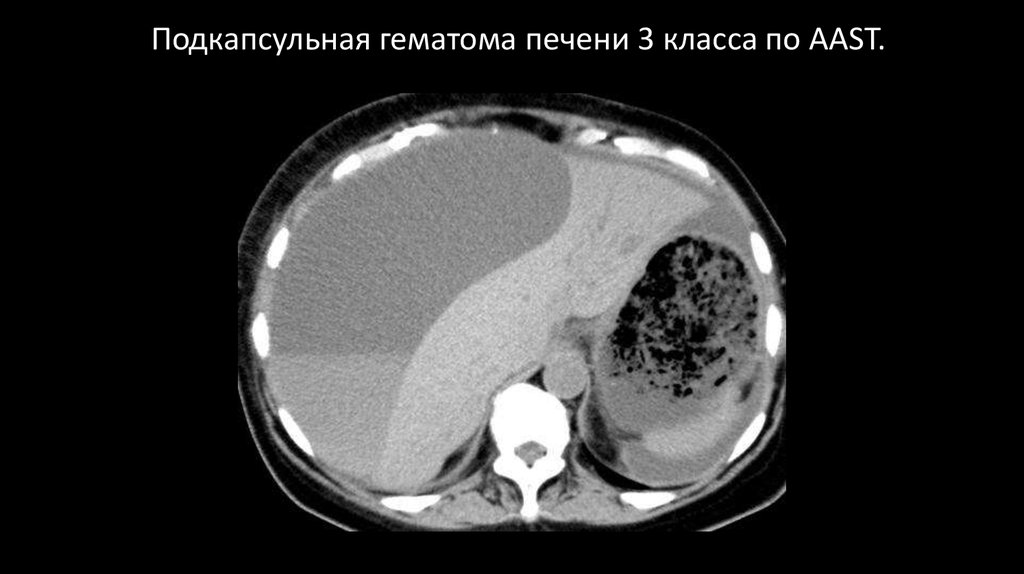

Подкапсульная гематома печени 3 класса по AAST.